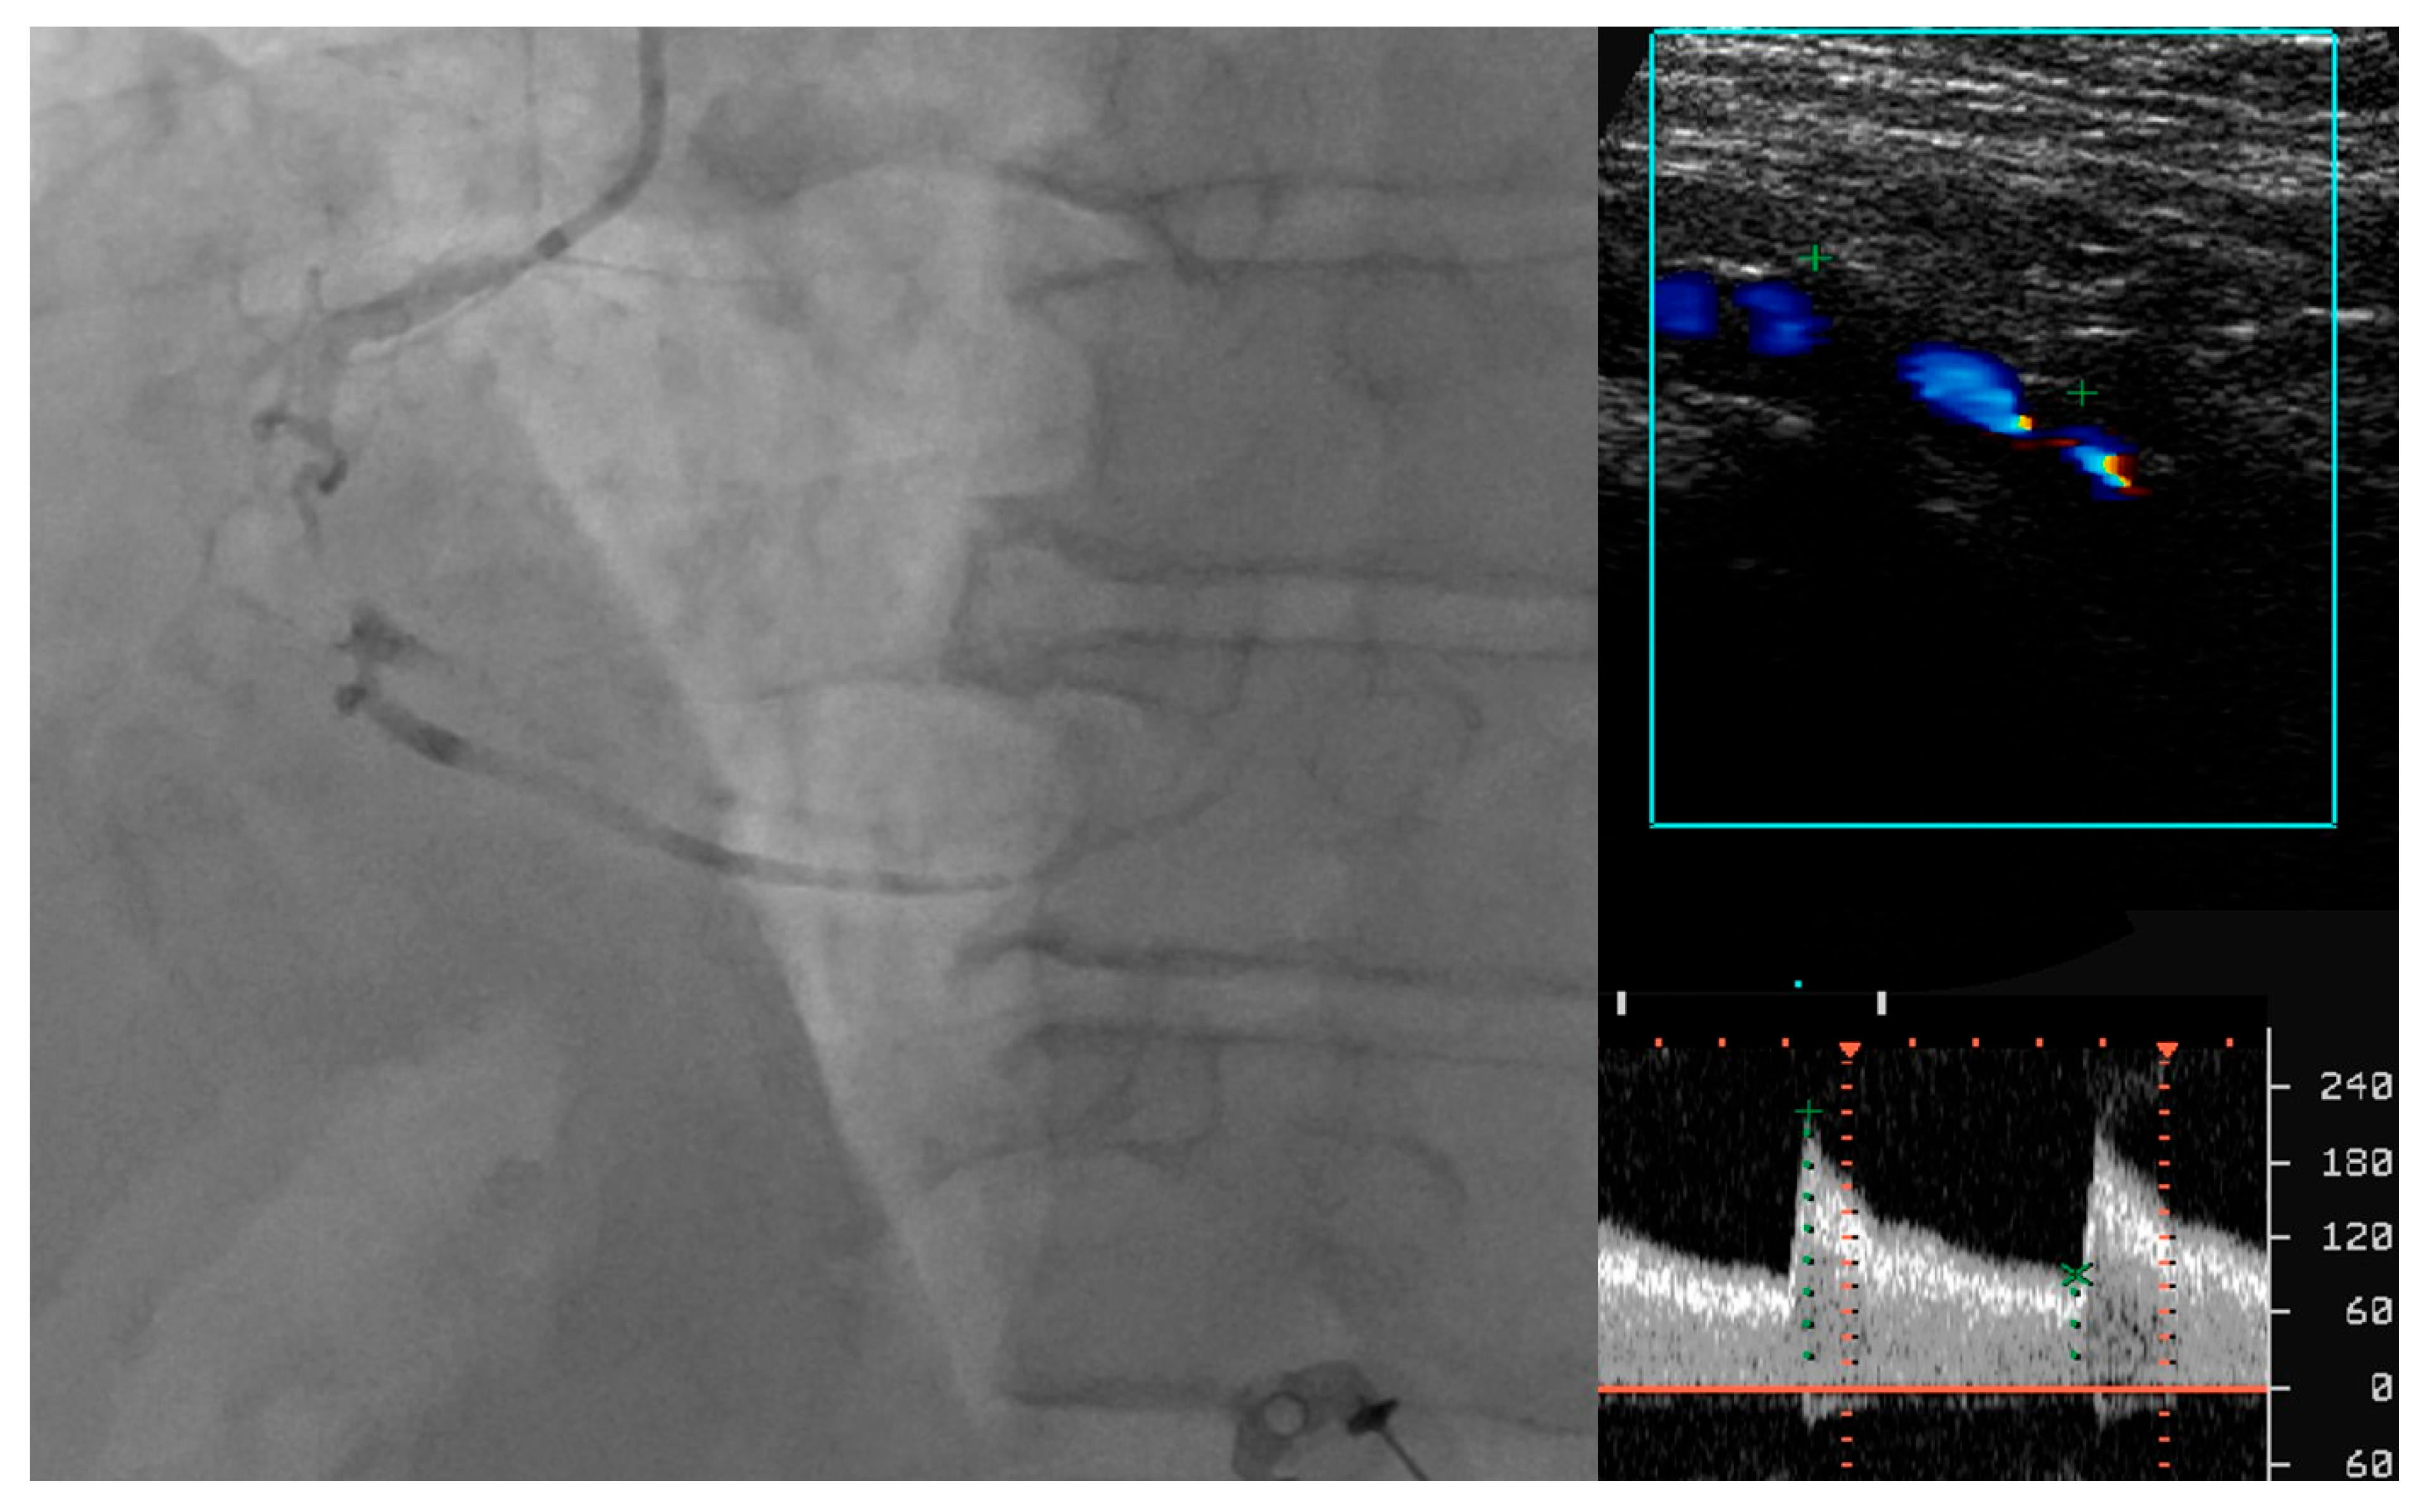

- Tătaru, D.A.; Olinic, M.; Homorodean, C.; Ober, M.C.; Spînu, M.; Lazăr, F.L.; Onea, L.; Olinic, D.M. Correlation between Ultrasound Peak Systolic Velocity and Angiography for Grading Internal Carotid Artery Stenosis. J. Clin. Med. 2024, 13, 517. [Google Scholar] [CrossRef] [PubMed]